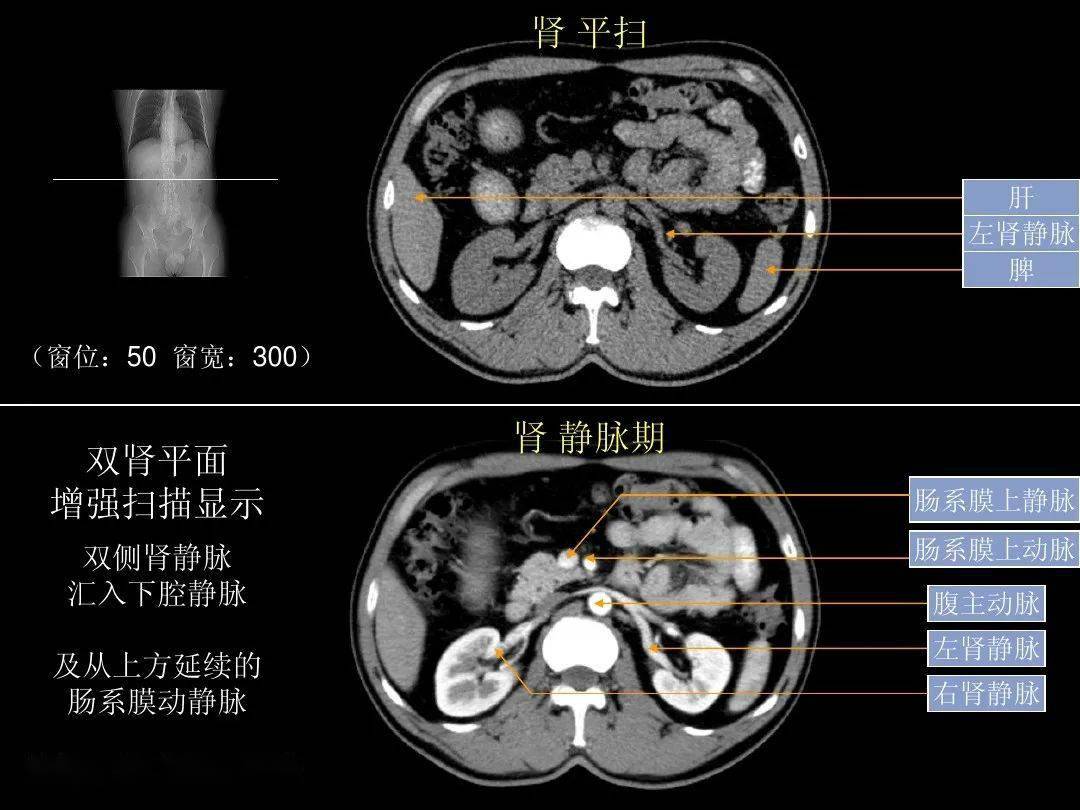

「腹部ct断层解剖」腹部ct扫描横断位解剖 详细标注,值得收藏